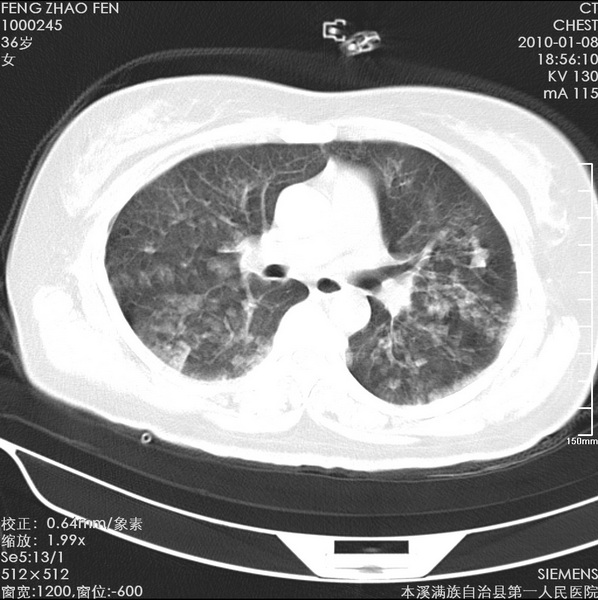

标题: CT24051:双肺多发斑片状阴影 [打印本页]

标题: CT24051:双肺多发斑片状阴影

女、36、咳嗽、咯血,余不详。